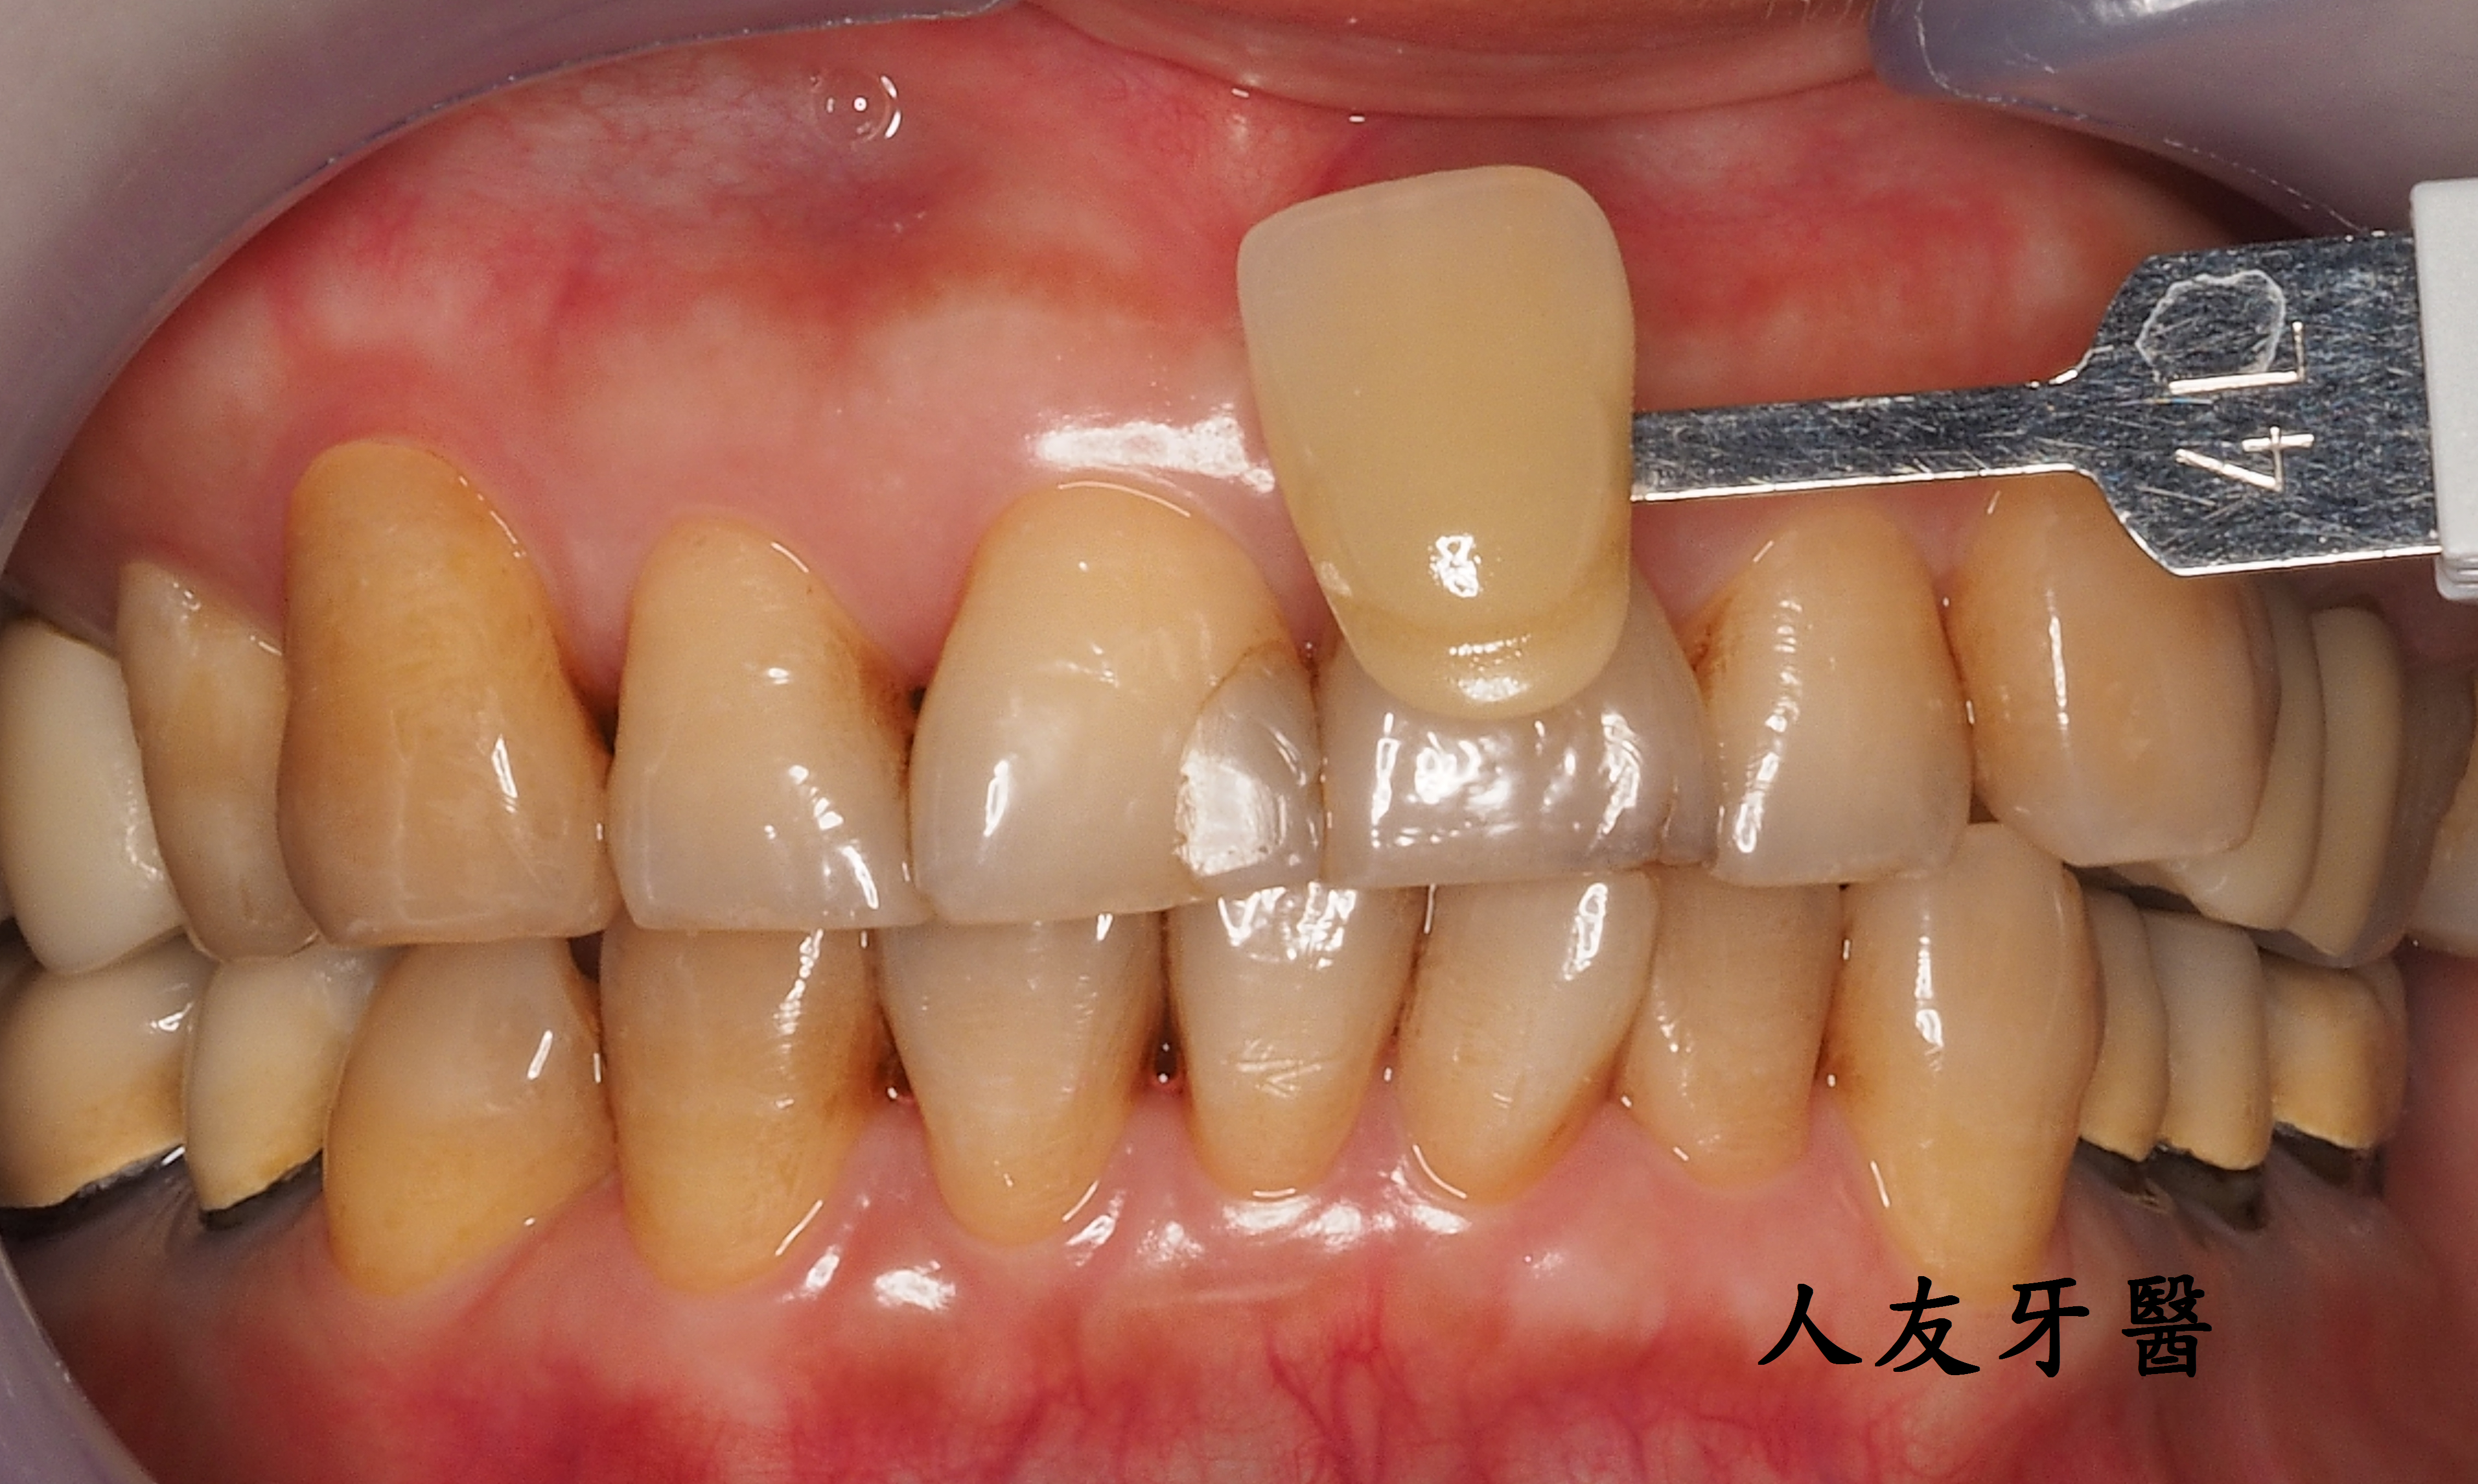

案例分享

有一位26歲女患者訴說她以前洗牙很容易敏感、會痠,但經過本診所進行的舒適型噴粉淨白方式,反而讓她驚訝為什麼不會痛、不會痠,甚至可以改善長期下來愛喝茶、咖啡導致的深層茶垢,這是因為我們使用相較於傳統清潔方式不同地方所在。

左為治療前 右為治療後